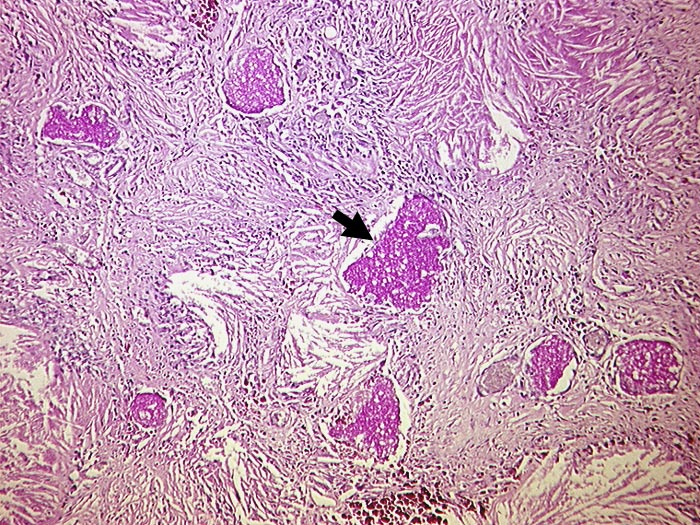

Chronische Pneumocystis jirovecii Pneumonie

Vernarbung des Lungeninterstitiums mit herausgelösten Cholesterinkristallen und PAS positiven schaumigen Einschlüssen. Diese enthalten zahlreiche Erreger.

AIDS. HIV Positivität bekannt seit 2 Jahren bei iv Drogenabusus.